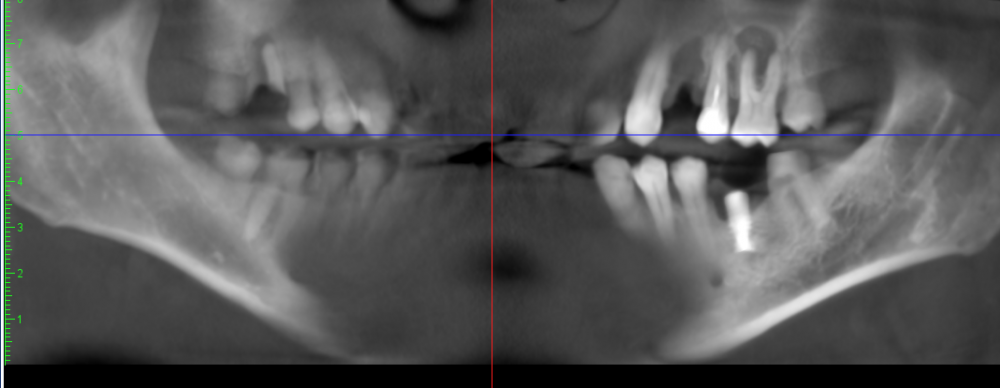

Папа Карло Опубликовано 13 июля, 2021 Поделиться Опубликовано 13 июля, 2021 Здравствуйте. Предлагают удалить зуб 2.6, причина воспаление на корне, проникающее в гайморову пазуху. Зуб не беспокоит вообще, не леченый (с соседними 2.4-2.5 были проблемы). Что можно сделать кроме удаления? Ссылка на комментарий

Bier Опубликовано 13 июля, 2021 Поделиться Опубликовано 13 июля, 2021 можно полечить эндодонтически. а имплантат внизу - удалять Ссылка на комментарий

St. Опубликовано 5 августа, 2021 Поделиться Опубликовано 5 августа, 2021 26 нормальный перспективный зуб, лечите. + соседний 25 нуждается в перелечивании каналов Ссылка на комментарий